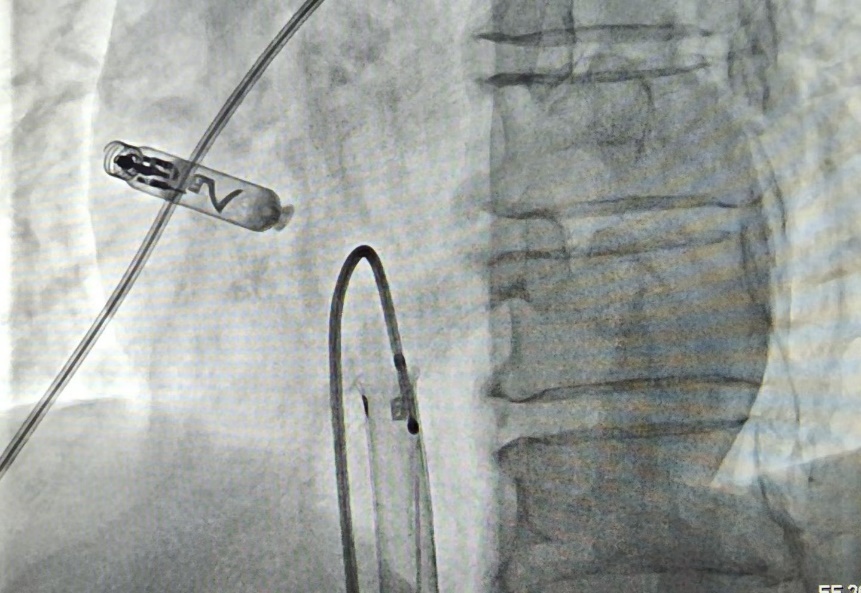

手术中,曲新凯主任与孔琤琦副主任医师通过患者大腿根部的股静脉,将起搏器顺利送至心脏右心耳——这里是心房最合适的起搏位置。借助起搏器头端的双螺旋设计,医生将其像螺丝一样轻轻旋入心耳组织,实现牢固“锚定”。整个手术过程不到一小时,术后测试显示起搏器工作一切正常。